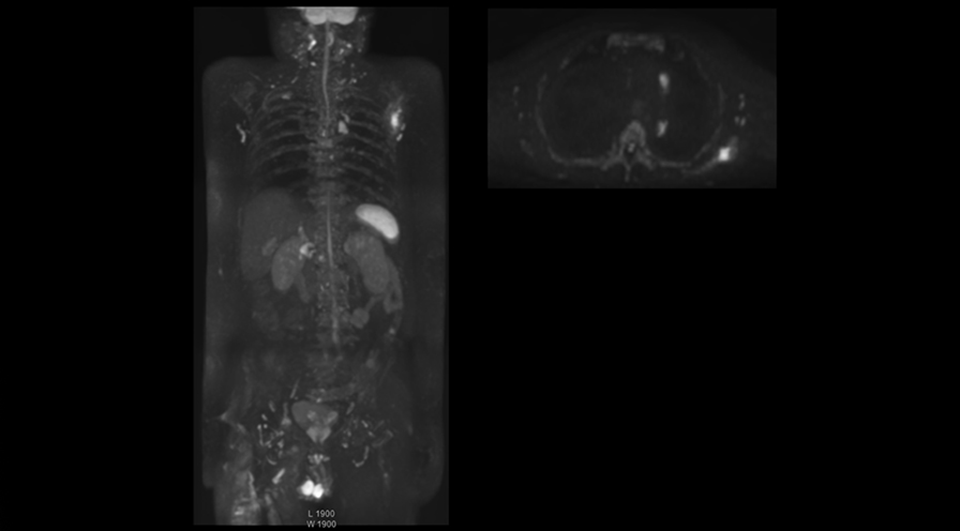

“The DWIBS sequence’s value in oncology cases is due to the high contrast it creates between lesions and surrounding tissue. Whole body DWI is requested by physicians who need to clarify TNM staging or determine therapeutic strategies, oncologists in need of diagnosis or follow-up scans, surgeons who need to see the presence of distant lesions that are sometimes difficult to detect by CT before surgery, and urologists for the evaluation of bone lesions, and the effect of chemotherapy and radiotherapy.”

After implementing the improved whole body protocol, the radiology team initially did not see a large increase in referrals, although Dr. Nobusawa saw clinical cases where the DWIBS images provided him valuable information for diagnosis. This is why Dr. Nobusawa and Mr. Naka started to actively educate referring physicians about the value of whole body DWIBS. They organized several presentations for physicians in the hospital, where they explained how DWIBS can be of value in oncology patients. The information it provides can be useful for physicians when staging cancer, as well as when determining or adjusting treatment strategy. Mr. Naka remembers some cases where DWIBS provided remarkable information. “In one example, DWIBS visualized bone lesions that could not be seen on PET or SPECT. In another case we had found a bone lesion when a normal L-spine scan for narrowing of the disk space was done. One extra DWIBS scan (2 stations, 8 minutes) demonstrated a lesion that later was confirmed to be the primary region of cancer.”